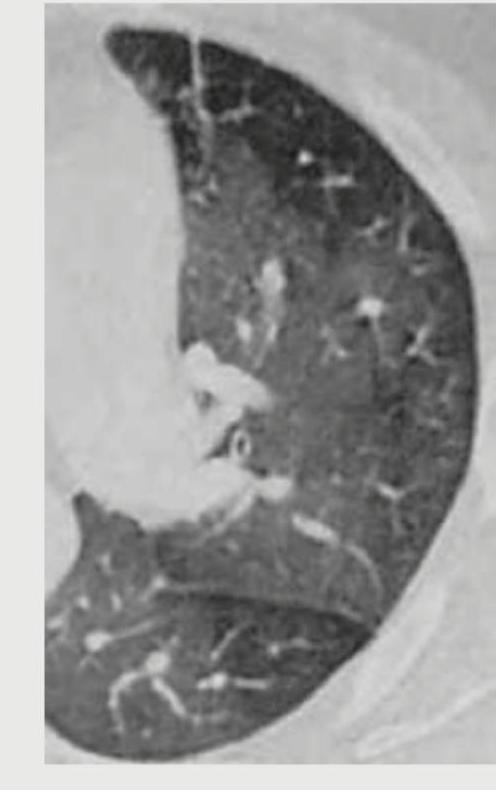

Explanation: ***End inspiratory phase*** - In the **end inspiratory phase**, the lungs are maximally expanded and appear quite dark (lucent) on CT, indicating a high volume of air. - The image shows expanded lung fields with numerous scattered opacities, which are better visualized against the well-aerated lung parenchyma, consistent with maximal inspiration. *End expiratory phase* - In an **end expiratory phase** CT, the lungs would appear smaller and denser due to reduced air volume, and structures would be more crowded, which is not seen here. - Expiratory CTs are typically used to detect **air trapping**, where areas of the lung remain abnormally lucent despite exhalation. *Mid inspiratory* - While showing some degree of lung expansion, a **mid inspiratory phase** would not demonstrate the maximal lucency and full expansion evident in the provided image. - It would be an intermediate state between maximal inspiration and expiration, with less overall lung volume than what is depicted. *Cannot be determined* - The distinct **appearance of the lung fields**, characterized by their large volume and lucency, strongly indicates the phase of respiration. - The visualization of scattered opacities suggests that imaging was performed to best demonstrate these findings within maximally inflated lungs.